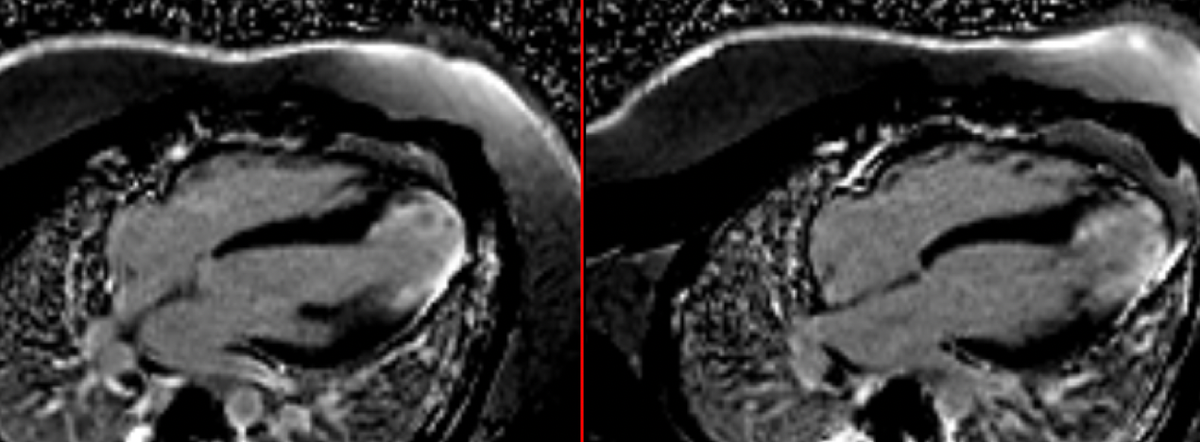

Apical HCM- Revisited

This post is for subscribers only